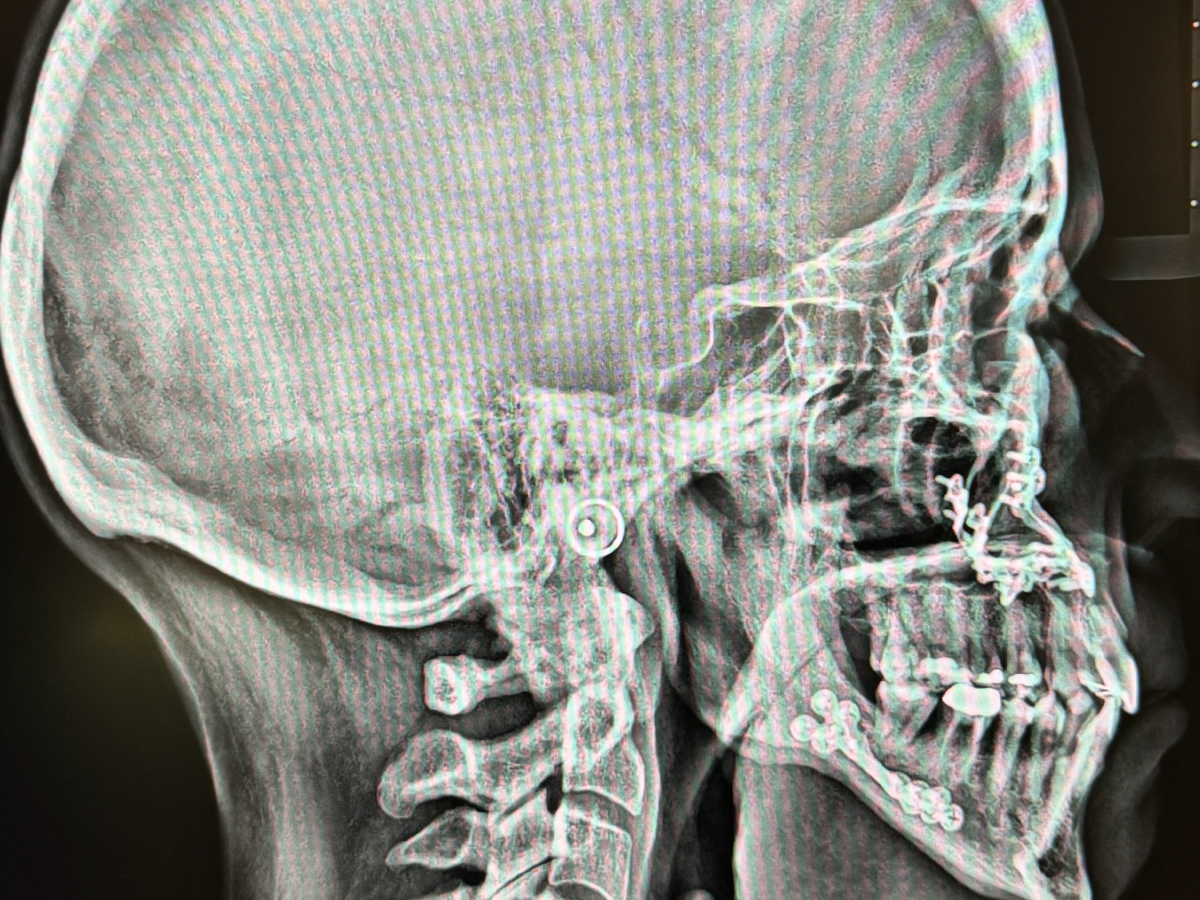

In January 2024, I had surgery on my jaws to alleviate obstructive sleep apnea. Maxillomandibular advancement surgery , or MMA, is a process in which the surgeon cuts both jaws and moves them forward, keeping them in place with several titanium plates and screws. The goal is to open up the throat for better breathing while asleep. The surgery took 7.5 hours. I went into it both scared and excited—MMA is the last hope for someone who can't tolerate CPAP or doesn't qualify for the Inspire implant, and it took almost a decade to get to this point. My breathing and snoring had gotten so bad, it was time to do something drastic. Something drastic with an over-90 percent success rate, that is.

The photo above was shortly after I woke up in my hospital room post-surgery. I knew the second I was awake that my breathing was significantly better. The following months were a roller coaster of extreme pain, numbness, and liquid meals. Now, 437 days post-surgery, I still have some numbness, but it's so much better than it was and I have absolutely no regrets. Who knew that breathing was so awesome!!